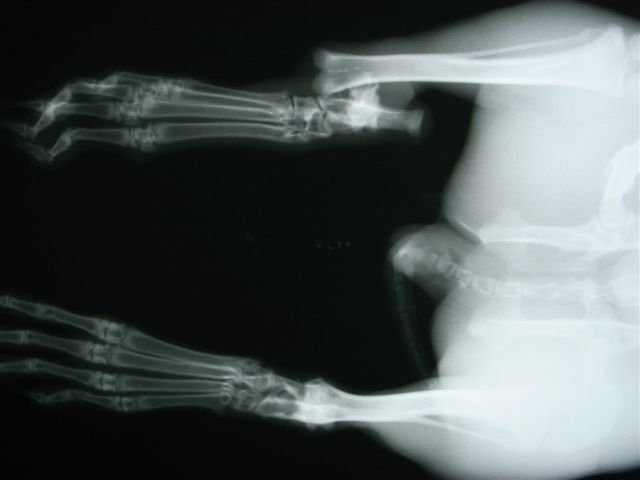

右頚骨の骨端線で骨折。

骨折する場所は太股の骨(大腿骨)、すねの骨(頸骨)、背骨(脊椎)です。後ろ足の力が強いために起こります。足の骨の場合、骨の中に金属の棒(ピンニング)やプレートで固定をして外側から固定をして、動かないようにケージに入れておきます(ケージレスト)。1ヶ月から2ヶ月ぐらいかかると思ってください。

うさぎの骨は簡単に骨折します。俊敏な動きを維持するために、骨が非常に軽く出来ているのですが、そのために強い衝撃を受けるとあっさり折れてしまいます。

だっこしていて落下したときにも折れますし、びっくりしてパニックに陥り、ケージの金網に足が挟まったり、あるいはケージを蹴り上げた衝撃などで勝手に折れてしまうこともあります。